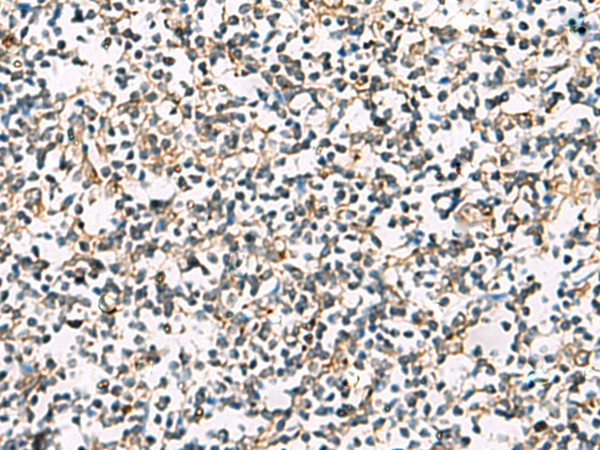

IHC positive control: |

Human tonsil |

IHC Recommend dilution: |

25-50 |